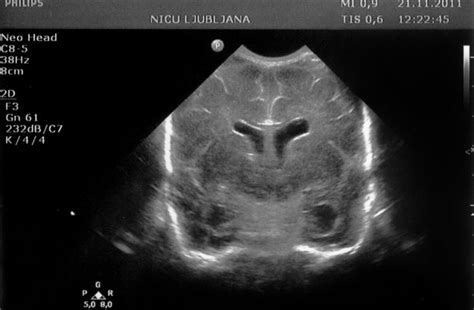

- Ultrazvok trebuha: To je ključna preiskava za potrditev piometre. Omogoča vizualizacijo maternice, njene velikosti, debeline sten ter prisotnosti tekočine ali gnoja v njej.